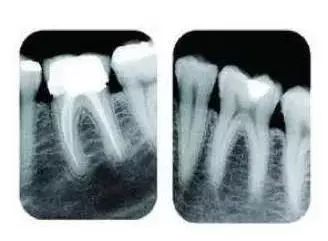

常见的牙科放射检查包括曲面体层片( 全景片 )、小牙片、头颅正侧位片、全头颅 CT、锥形束 CT( CBCT )等。由于牙齿下部隐藏在牙槽骨中,口腔医生要了解牙齿的整体情况就需要拍摄全景片;

要了解个别牙根及周围变化,则选择拍摄小牙片。医生要判断牙槽骨是否符合种植条件,或者了解埋伏阻生齿的三维位置以及其他颌骨内病变组织的形态大小时,则需要进一步拍摄 CBCT 。